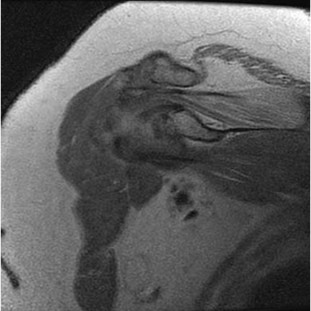

Tarsal coalitions occur when primitive mesenchymal cells fail to differentiate and form the

normal articular separations between the tarsal bones of the hindfoot. Overall incidence is difficult to determine because many affected people are minimally symptomatic or asymptomatic. Symptomatic tarsal coalitions typically present in adolescents as a painful flatfoot; however, there are a number of possible presentations, and occasionally symptoms do not appear until adulthood. Most tarsal coalitions are between the calcaneus and the navicular (CN) and the talus and the calcaneus (TC). Although most TC coalitions are across the middle facet, posterior facet coalitions do occur. Plain radiographic evaluation of suspected tarsal coalition is the mainstay for diagnosis. However, coalitions can be bony or fibrous, and making the diagnosis can be difficult. The addition of CT images to distinguish bony definition and MR images to decipher soft tissue can aid in diagnostics. Bony coalitions appear as definite bony bridging between the bones, while fibrous coalitions are suspected when distortion of the bony anatomy is seen. Bony coalitions are best seen on the oblique view (CN) and Harris axial view (TC). There are a number of secondary signs such as the anteater (AE) sign (elongation of the anterior process of the calcaneus as it extends to the navicular as seen on the lateral view [CN]). talar beaking (traction spur of the talar neck thought to result from abnormal stresses as seen on the lateral view [both CN and TN]), and the “C” sign (a continuous cortical contour from the medial talus to the sustentaculum tali [ST]) as seen on the lateral view (TC). A number of newer signs are not as well known, such as a broad mediolateral dimension of the navicular on the anteroposterior (AP) view (the

navicular is wider than the talar head [CN]), nonvisualization of the middle facet on the lateral view (TC), the brick sign (a normal ST is flat, but a distorted ST is enlarged and curved [CN]), and a tapered lateral navicular bone as seen on the AP view (the medial navicular [CN] is much thicker than the lateral navicular).

Figure 7a shows a mild flatfoot with lateral peritalar subluxation of the navicular. Figure 7b does not show an open MF and has a questionable C sign. Figure 7c shows that the opening between the calcaneus and the navicular appears normal without distortion. Figures 7d, 7e, 7g, and 7h show a lateral sloping distorted middle facet consistent with a middle facet coalition, and Figure 7f shows a normal posterior facet.